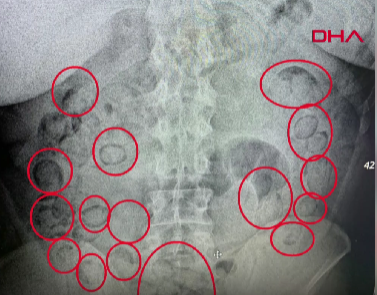

Şüpheli davranışları nedeniyle gözaltına alınan A.M., Aksaray Eğitim ve Araştırma Hastanesi’ne götürüldü. Burada çekilen röntgende midesinde yabancı cisimler tespit edildi. Yapılan tıbbi müdahale sonucu A.M.’nin midesinden 101 parça halinde toplam 433 gram uyuşturucu madde çıkarıldı.